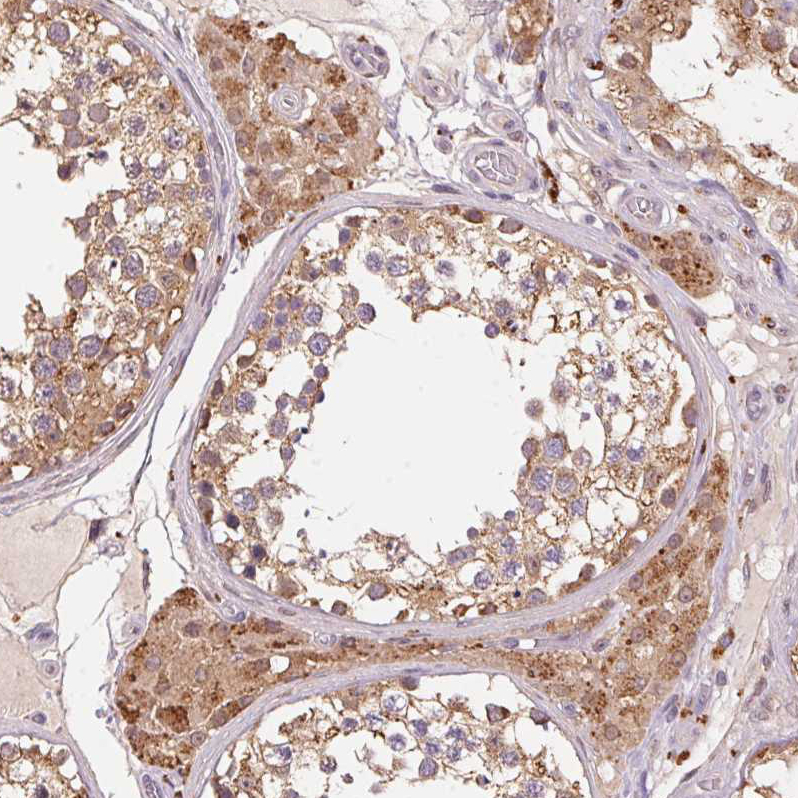

Immunohistochemistry analysis in human endometrium and skeletal muscle tissues using HPA061919 antibody. Corresponding ADH5 RNA-seq data are presented for the same tissues.